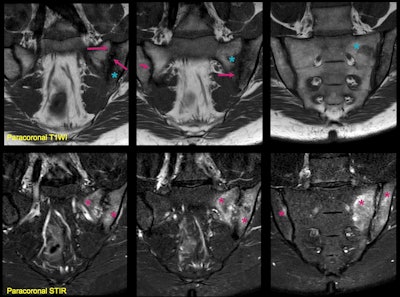

A 35-year-old woman presented with lower back pain, human leukocyte antigen B27+, and increased polymerase chain reaction. Paracoronal STIR shows extensive subchondral edema (asterisks) and increased signal intensity in the inter-articular line, reflecting effusion and synovitis in the left sacroiliac joint (SIJ); all consistent with active inflammation. Note that the changes are bilateral and asymmetrical with predominance of inflammatory changes in the left joint. Paracoronal T1WI shows structural including erosions, subchondral sclerosis (arrows), and early joint space loss. Note that some areas of osteitis/bone marrow edema are low signal in T1WI (blue asterisk), but not as low as sclerosis. Structural and inflammatory lesions can coexist, and SIJ involvement can sometimes be asymmetric or unilateral.